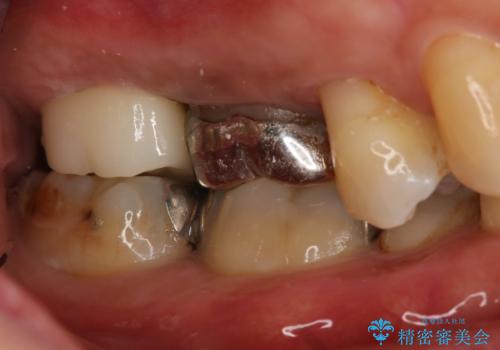

- 右上大臼歯の被せ物が取れたので作り直しを希望された患者様です。

被せ物は白くしたいとのことだったのでフルジルコニアクラウンでの治療を選択しました。

根管治療も必要だったので金属の土台を除去し、新しく土台を立て直した上で被せ物を装着しています。